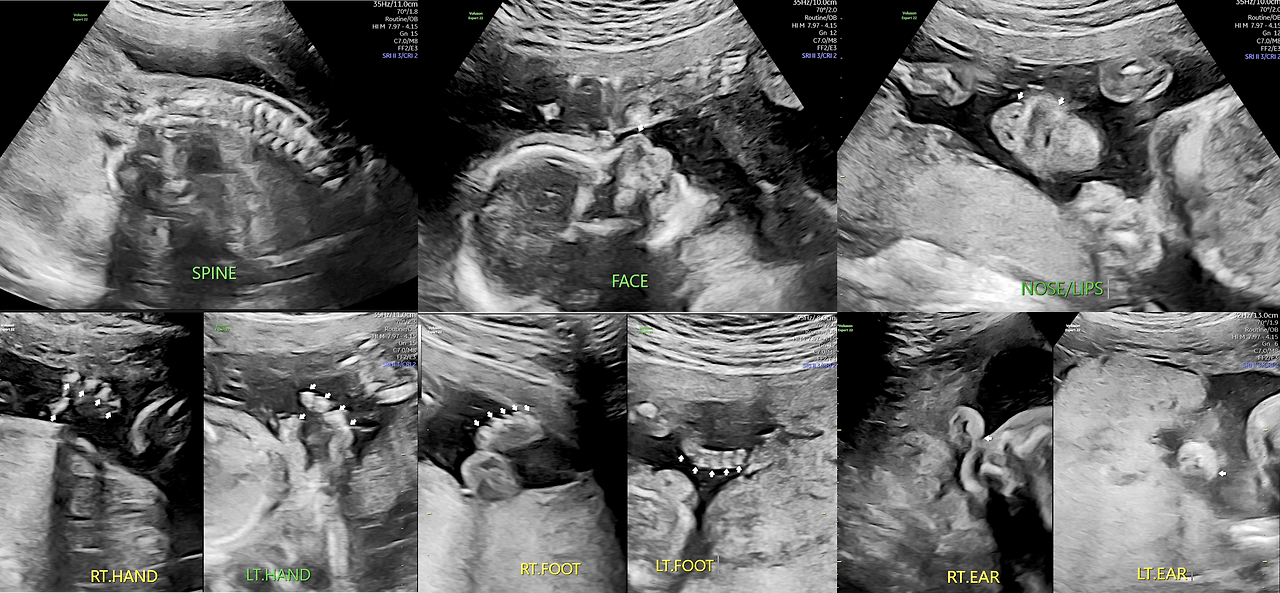

먼저 태아의 척추의 상태, 얼굴 윤곽, 코와 입술, 그리고 양손과 발가락의 개수, 귀가 보입니다.

제가 전문가는 아니지만 화면으로 볼 때는 다 문제가 없어 보이고, 특히 손가락과 발가락 5개는 또렷하게 잘 보이네요. 의사분도 정상이니 아무런 말이 없었겠지요.